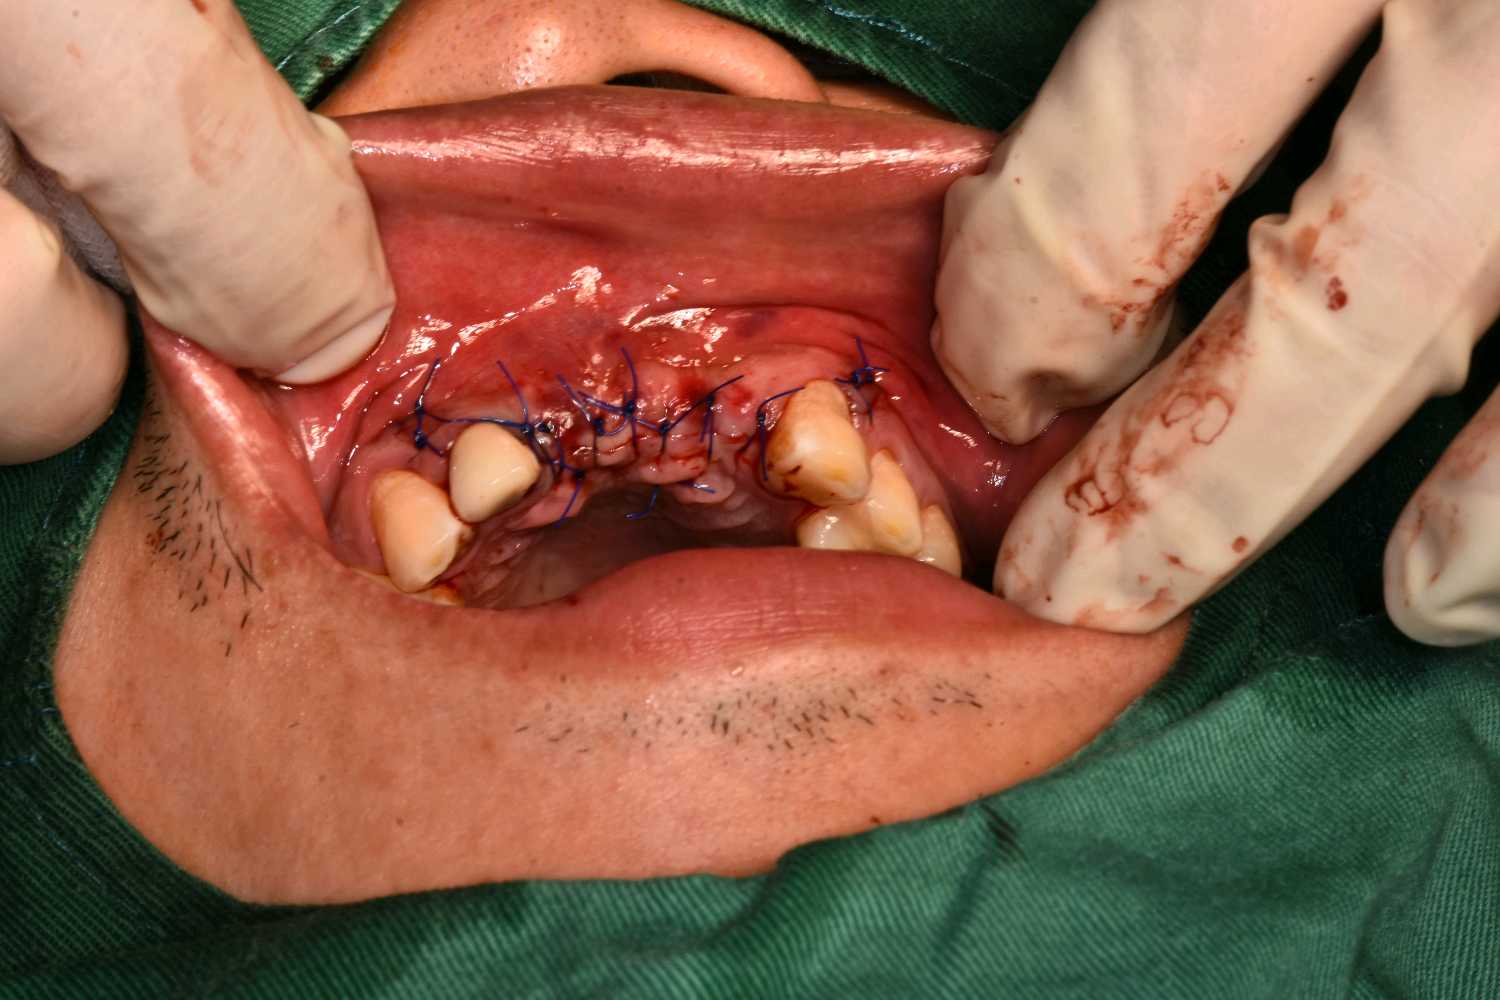

术后

图片发自160App